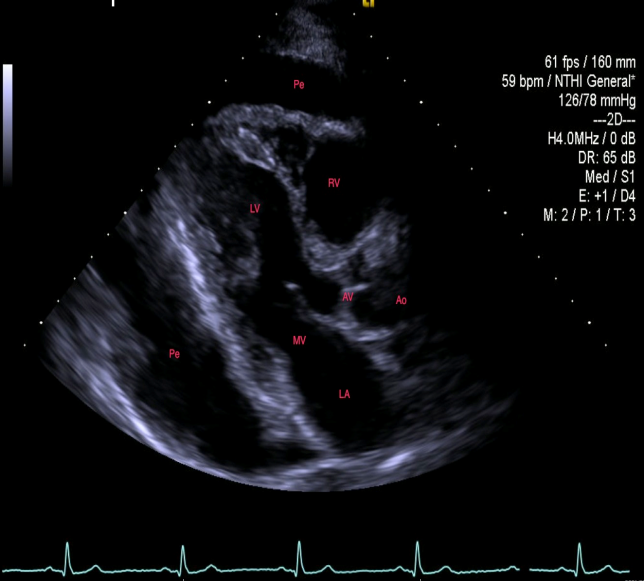

A 58-year-old woman presented with a symptomatic, massive pericardial effusion. Due to shortness of breath for over three months, she underwent percutaneous pericardial drainage (Fig. 1). She had no other significant medical problems.

1.5 liters of serous, odorless fluid was removed and the echo appearance normalized, showing only trace pericardial fluid and a well-preserved ejection fraction. However, within four weeks the effusion re-accumulated as shown in the CXR (Fig.2) and echo showed early tamponade.